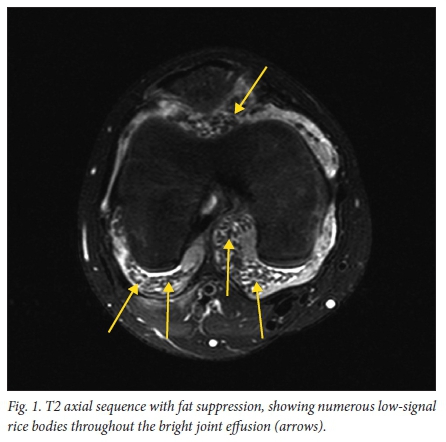

The MRI study was performed on a 1.5 Tesla Philips Intera MRI scanner. The scan showed a moderate joint effusion with extensive rice-body formation throughout all compartments of the knee joint (Fig. 1). This was evident as small rod-shaped areas of low signal on T1 and T2 sequences. Slightly larger pea-sized loose bodies were noted, mainly in the suprapatellar pouch. The post-contrast sequence also showed markedly enhancing synovium throughout the joint (Fig. 2), but no enhancement of the loose bodies. The articular cartilage appeared normal with no erosions or focal marrow oedema. Mildly prominent lymph nodes were noted in the popliteal fossa.